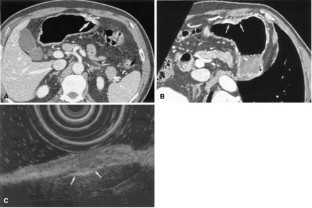

Figure 4